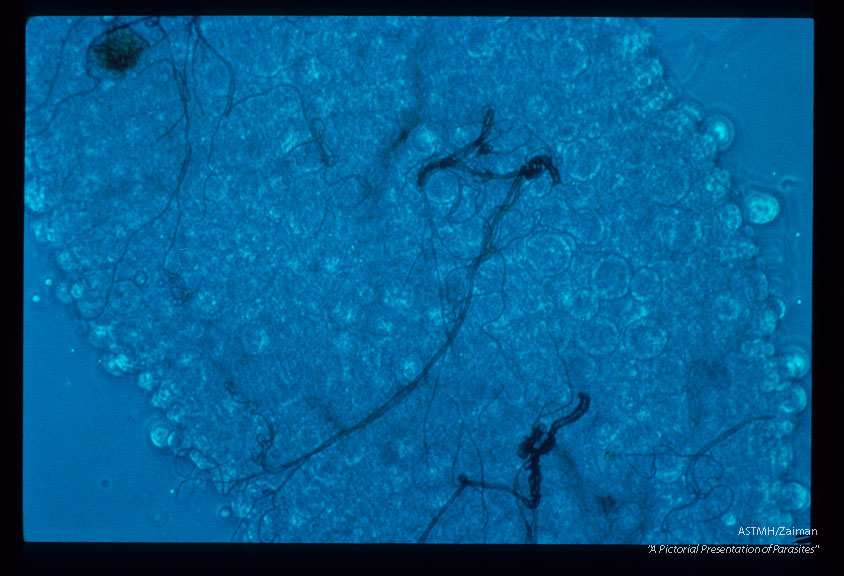

A parasite of wild turkeys. Oocysts on the midgut of the mosquito, Culex pipiens pipiens.

Plasmodium kempi

Description: A parasite of wild turkeys. Oocysts on the midgut of the mosquito, Culex pipiens pipiens.